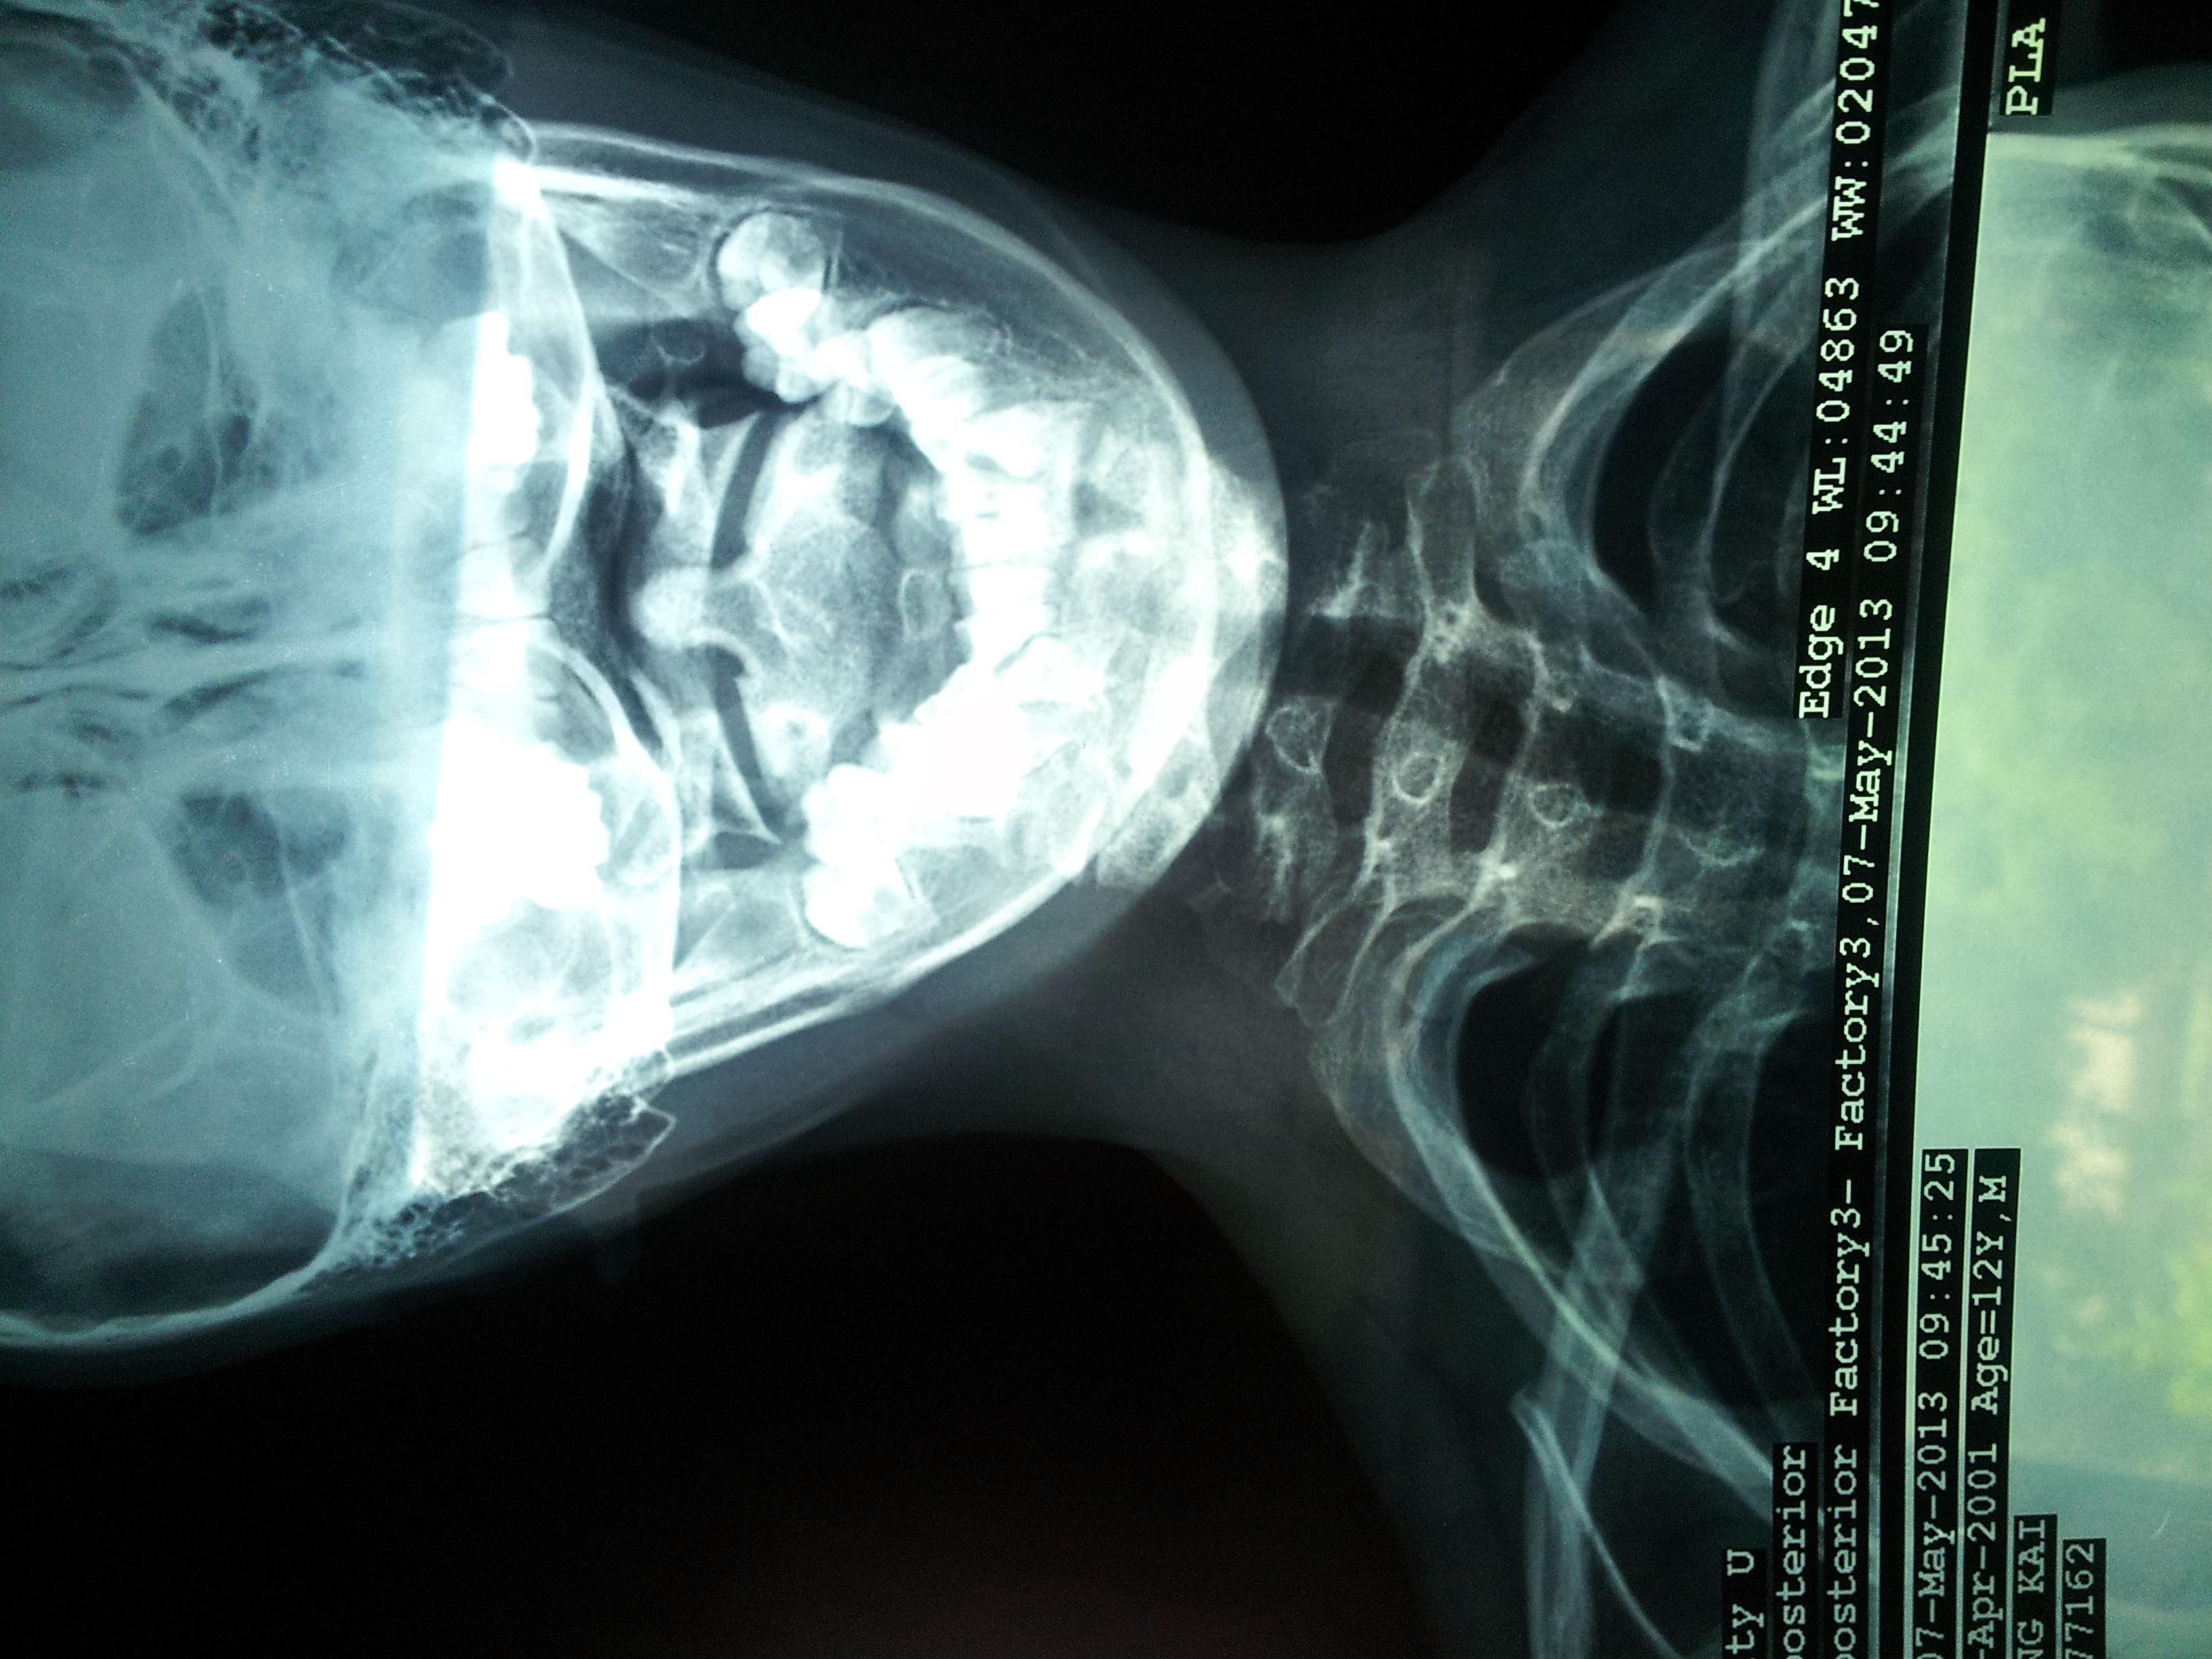

男,65岁左肩颈部肿物术后二个月复查,ct平加增示左斜方肌前巨大占位.

65岁男性,吸烟史30余年,近半年来颈部出现疼痛性肿块,ct扫描如图所示